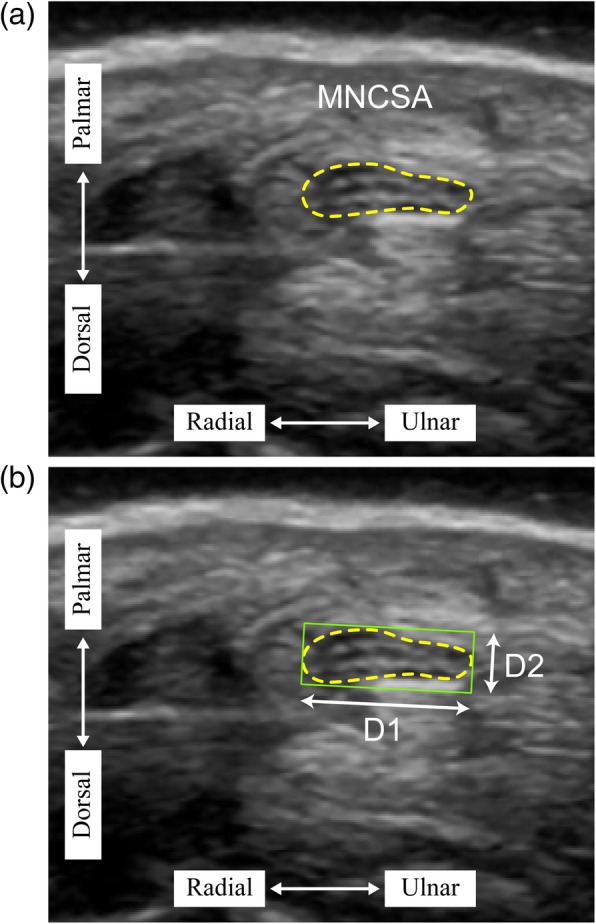

The underlying biomechanical factors of the active wrist and finger movements causing changes in the median nerve can be examined and analyzed using high-resolution ultrasound imaging technique [6–8]. The common use morphological measurements are cross-sectional area by tracing method (Fig. 1a) and diameter (longitudinal diameter, D1; vertical diameter, D2) of the nerve by minimum bounding rectangle method (Fig. 1b). The main objective is to extend the confirmatory study to our previous findings [9, 10] on the median nerve changes by comparing the differences of median nerve cross-sectional area (MNCSA) between young and elderly participants at different wrist angle.

Fig. 1.

Quantification of (a) median nerve cross-sectional area by tracing method and (b) median nerve diameter by minimum bounding rectangle

Ultrasound images were obtained via the LOGIQ e ultrasound system (GE Healthcare, Milwaukee, WI, USA) with a 12L-RS transducer (imaging frequency bandwidth of 5–13 MHz). The ultrasound protocol included wrist examination at 7 different passive wrist angle (neutral (0°); 15°, 30°, and 45° extension; and 15°, 30°, and 45° flexion) and the MNCSA was quantified using ImageJ (National Institutes of Health) [9, 10]. Our previous study indicated that active and passive wrist holding position did not cause significant differences in the measured MNCSA [12]. The median nerve was identified by the hyperechogenic rim and MNCSA was quantified by tracing along the hyperechognic rim (Fig. 1a) and median nerve diameter by minimum bounding rectangle method (Fig. 1b).